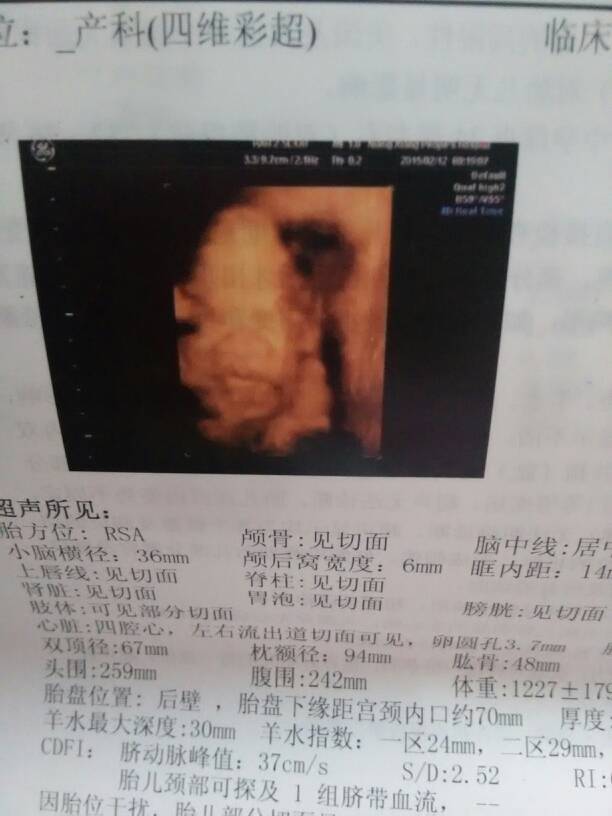

今天去做了四维,宝宝的脸看不清

你现在的彩超显示胎儿的数值符合孕六个月的月份,胎儿的部位显示不具体。建议你定期检查胎儿健康状况即可。

你好,怀孕22-26周是进行四维彩超检查的最佳时机,此时可清晰显示胎儿各部位脏器,了解胎儿生长发育情况,观察头,肢体及各脏器大体结构是否有畸形,建议孕期定期检查。